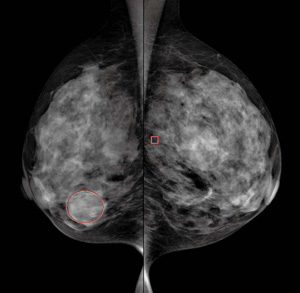

4.デジタル拡張性

GE CADの国内稼働実績は60台以上と,国内のCADの実績は市場において非常に高いシェアを占めている。撮影された画像はCAD本体に自動転送され,関心領域に,石灰化の疑いおよび腫瘍の疑いのある領域にマークが付き,すぐに観察可能となるため,読影の効率アップと見落としによるリスク低減に大きく貢献している(図3)。

図3 CAD